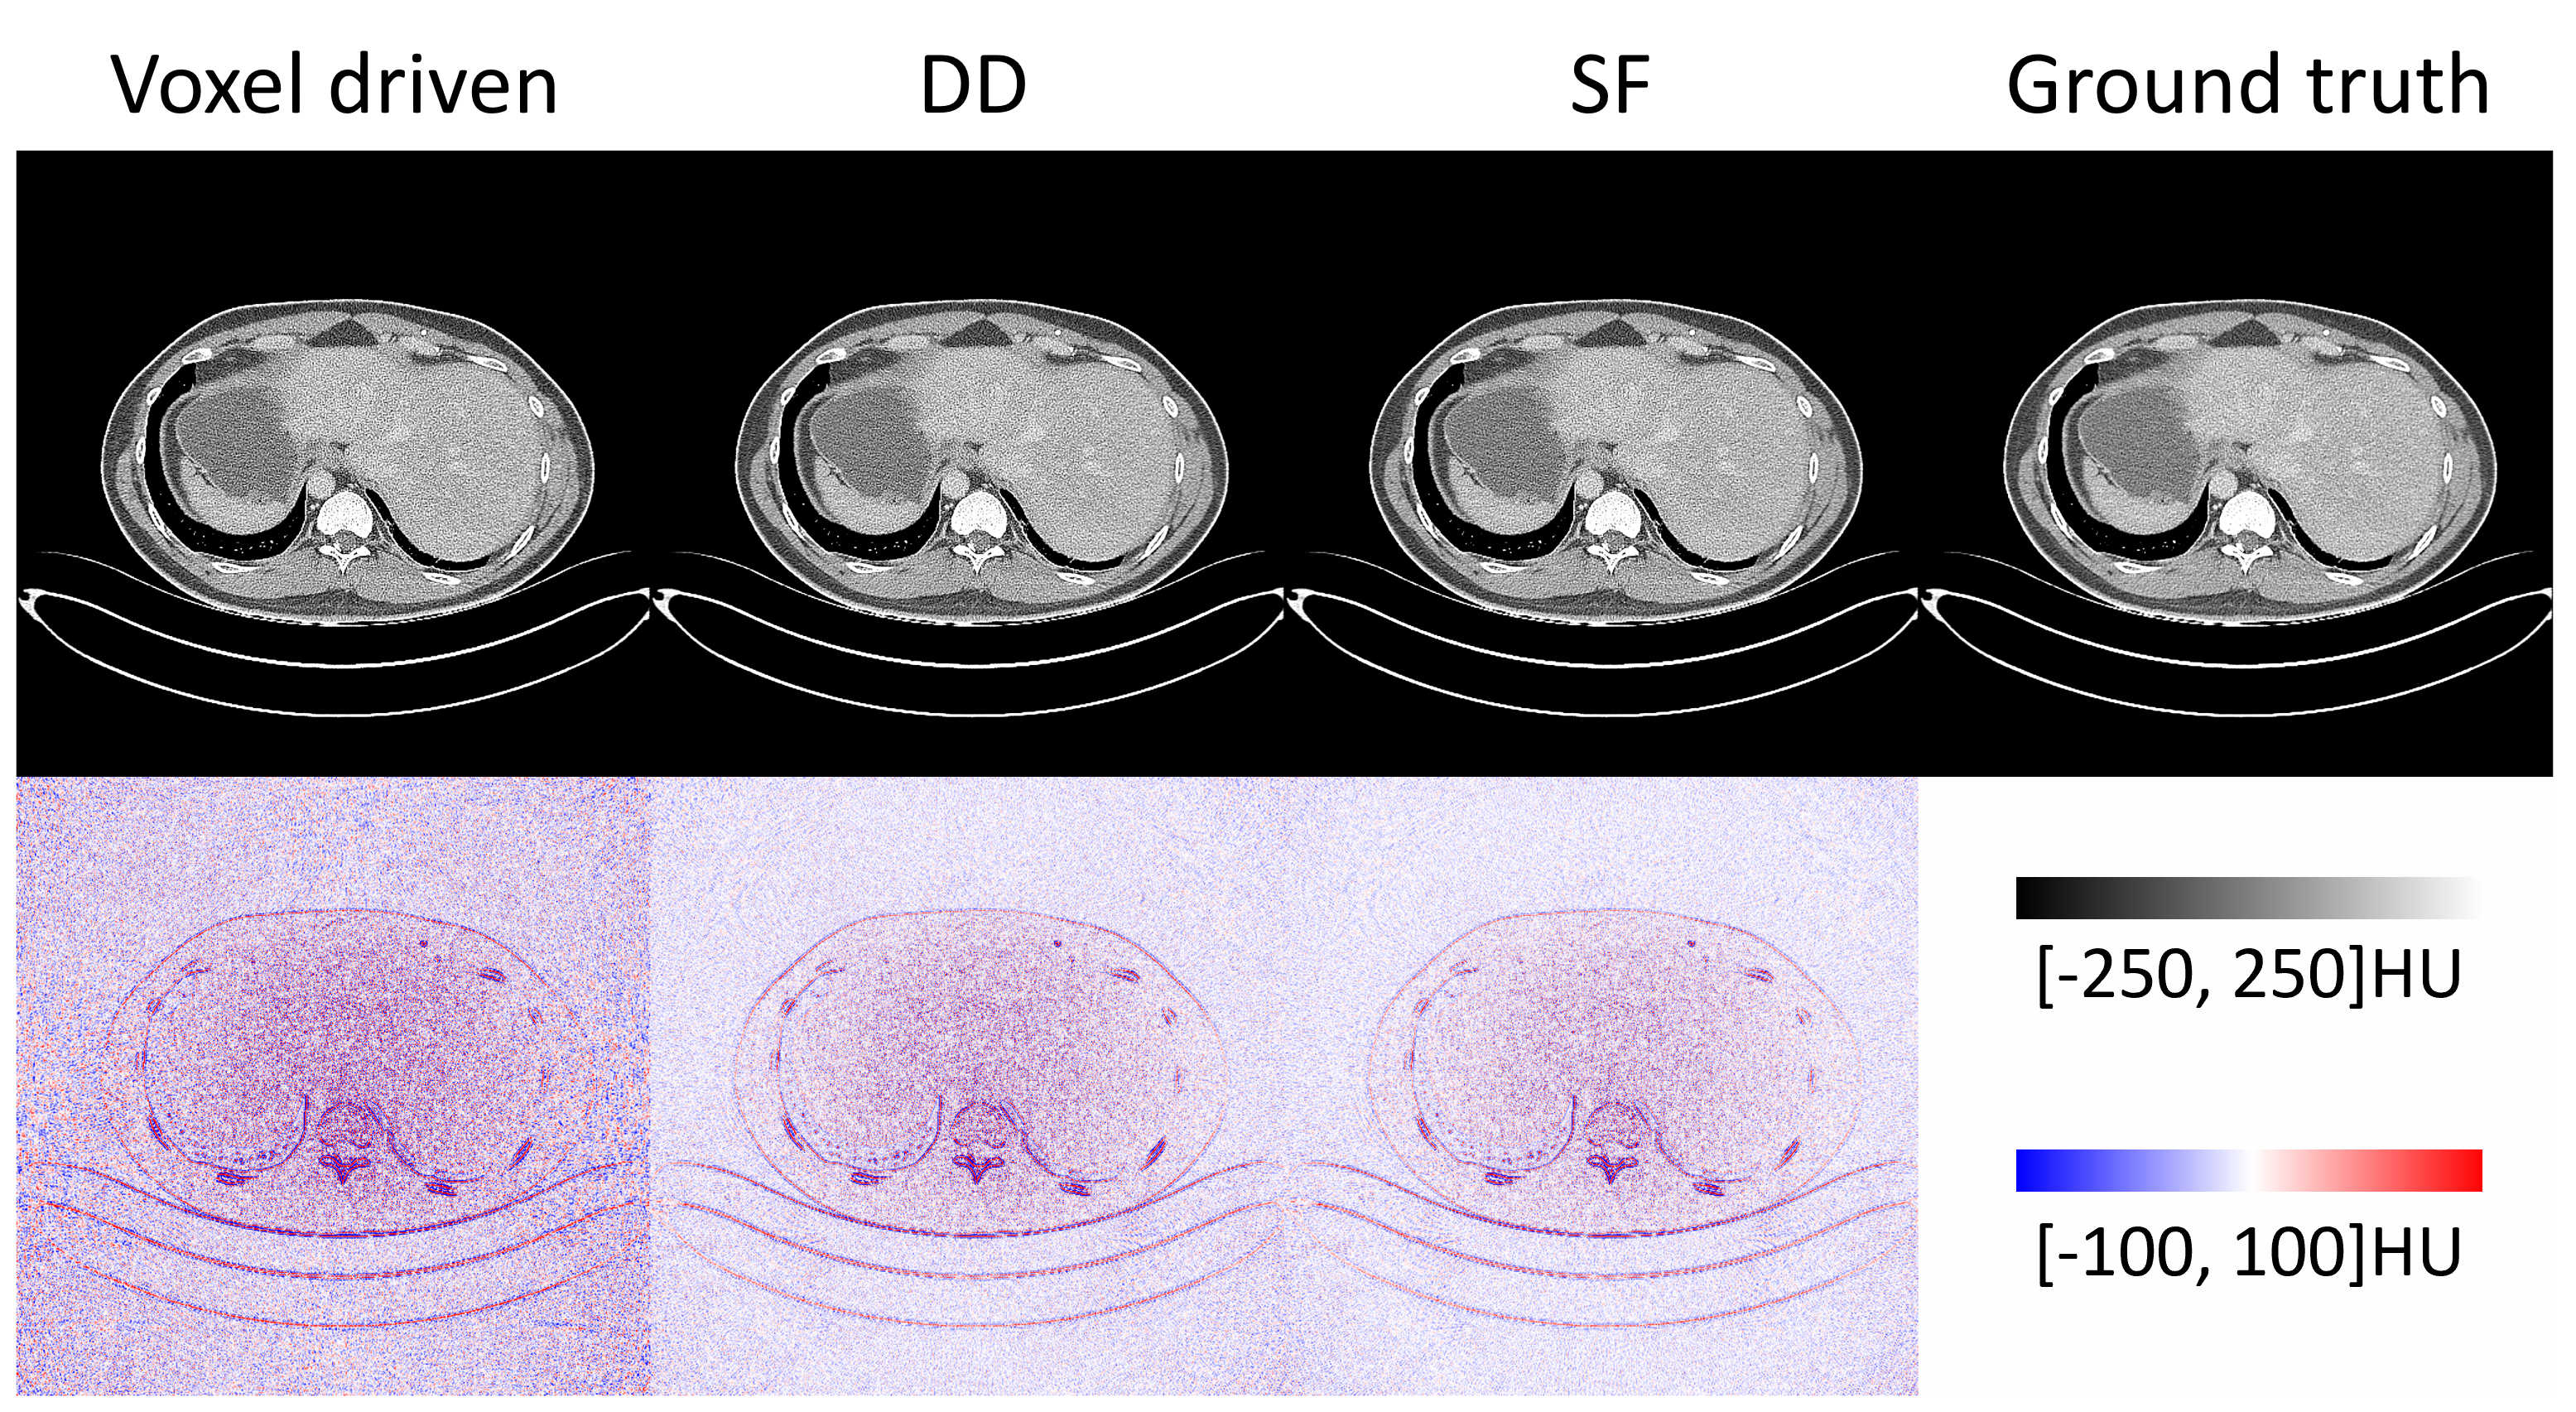

Next, we validate the CTorch projector for a curved detector using public sinogram data from the AAPM MAR challenge[23]. This dataset simulates 1D projections acquired using a curved detector with a 1.25-pixel lateral offset. The reconstruction results are summarized in Fig. 7. The reconstructed images obtained with different projectors closely match the ground truth. The corresponding error maps further illustrate that no significant geometric distortions are present in the reconstruction, with errors primarily concentrated around sharp edges. These errors may be attributed to differences in the applied filtering function.

Figure 6: FBP reconstruction using the curved-detector projections from AAPM MAR challenge dataset. The bottom row display the difference images between CTorch reconstruction and the ground truth.